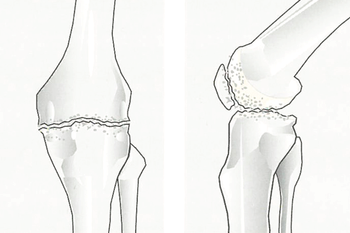

Glideflatene i kneet (leddflatene) består av leddbrusk. Leddbrusken er svært glatt og elastisk og dekkjer overflatene på beinet som dannar leddet.

Som ung er leddbrusken i kneet opptil 8 mm tjukk. Etter kvart som du blir eldre, vert leddbrusken slitt. Det er viktig å vite at leddbrusken ikkje er i stand til å reparere seg sjølv. Når brusken er slitt kan det ikkje danna seg ny brusk i leddet. "Tennene skal vare heile livet", seiast det. Dette gjeld på same måte for leddbrusken.

Når brusken er nedslitt snakkar vi om slitasjegikt eller artrose.

Dei nedslitte leddflatene skaper kraftig irritasjon i leddet. Dette fører til smerte og hevelse. Hevelsen skuldast at det irriterte kneleddet danner meir leddvæske enn normalt. Etter kvart som artrosen auker, kan sjølve leddet forandra seg. Det dannar seg beinpåleiringar og forkalkningar, ein kan bli hjulbeint eller kalvbeint. Slitasjen må ikkje nødvendigvis omfatta heile kneet. Ofte vil berre delar av leddet utvikla slike forandringar.